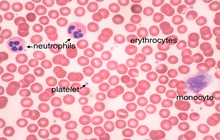

- General and specialized tissue and cell staining

- Prepare educational slides for students from all available tissues

Histological methods includes sample processing in the pathology laboratory, preparation of the slide and its examination under a microscope, sample fixation, molding, microtome cutting, staining and assembly of the slides.